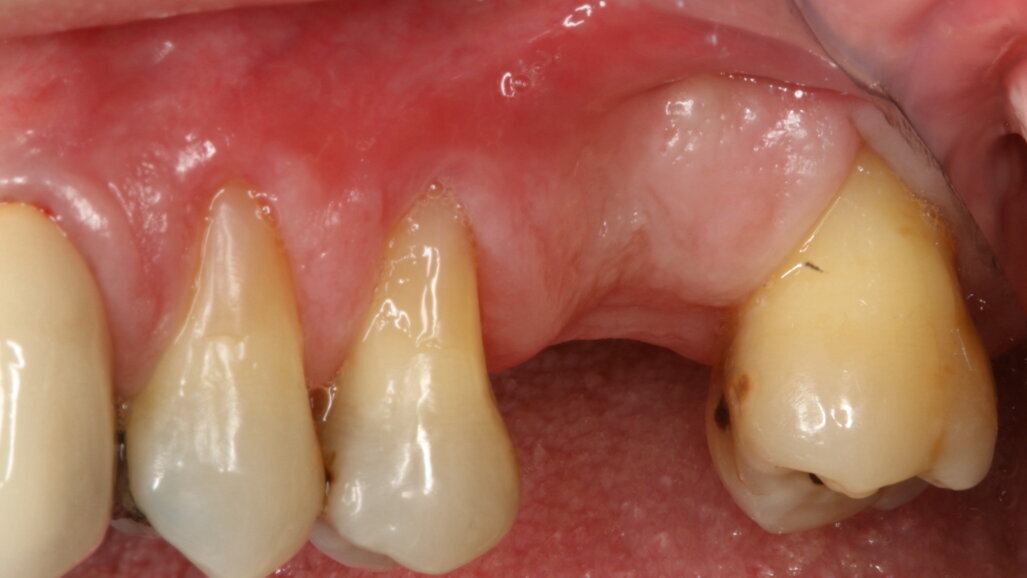

Le radiografie a tre mesi hanno evidenziato un buon rimaneggiamento del biomateriale e segni di neoformazione ossea dal pavimento del seno, confermando le proprietà osteogeniche di OsteoBiol Putty. A sei mesi, l’osso innestato risultava completamente rigenerato, permettendo la finalizzazione protesica con una corona in disilicato di litio cementata su cappa in titanio (Figg. 6-13).

Fig. 8_Guarigione dopo 4 mesi.

Fig. 9_Guarigione dopo 4 mesi con focus sui tessuti molli perimplantari.